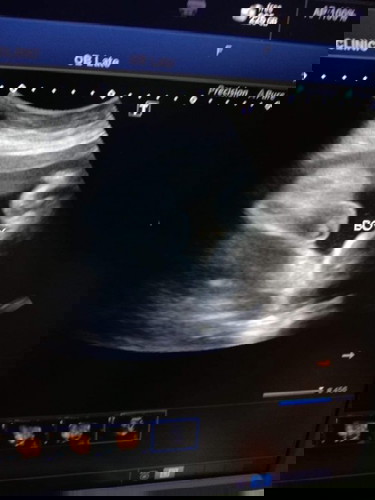

ผู้ชายจริงหรือ?

อยากถามแม่ๆค่ะ ไปซาวด์มา หมอบอกได้ผู้ชาย แต่แม่มองยังไงก็มองไม่ออกเลยค่ะว่าเป็นผู้ชาย เพื่อนๆว่าผู้ชายหรือผู้หญิงคะ 😂

ใบซาวด์เขียนว่าบอยน่าจะชายค่ะแม่